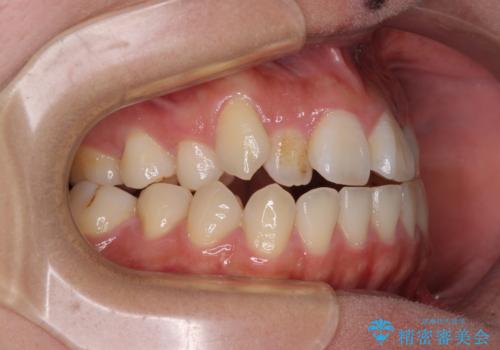

- 前歯の開咬と、上顎前歯の八重歯やデコボコを気にして来院された患者様です。

上顎歯列が狭窄していたため、急速拡大装置により上顎骨を側方に拡大し、その後ワイヤー装置にて矯正治療を行うこととしました。

上顎骨を拡大することで、八重歯やデコボコを歯列に収めることができ、下顎の歯が外に位置していた奥歯の咬み合わせも改善することができました。